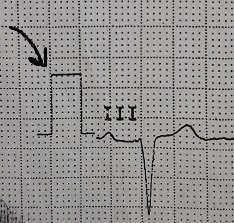

This is the standardization mark in the ecg.We have to look at this vertical mark in the e c g and see the mark exactly covers two big squares.Standard calibration is 25 mm/second,0.1millivolt per millimeter.